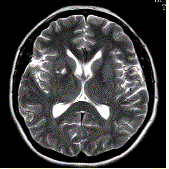

问题 男性,55岁。临床偶尔头晕,无高血压,糖尿病病史。MRI显示如下图。 可能的诊断是

选项 A.血管周围间隙 B.腔隙性脑梗死 C.神经上皮囊肿 D.脑囊虫 E.囊性肿瘤

答案 A